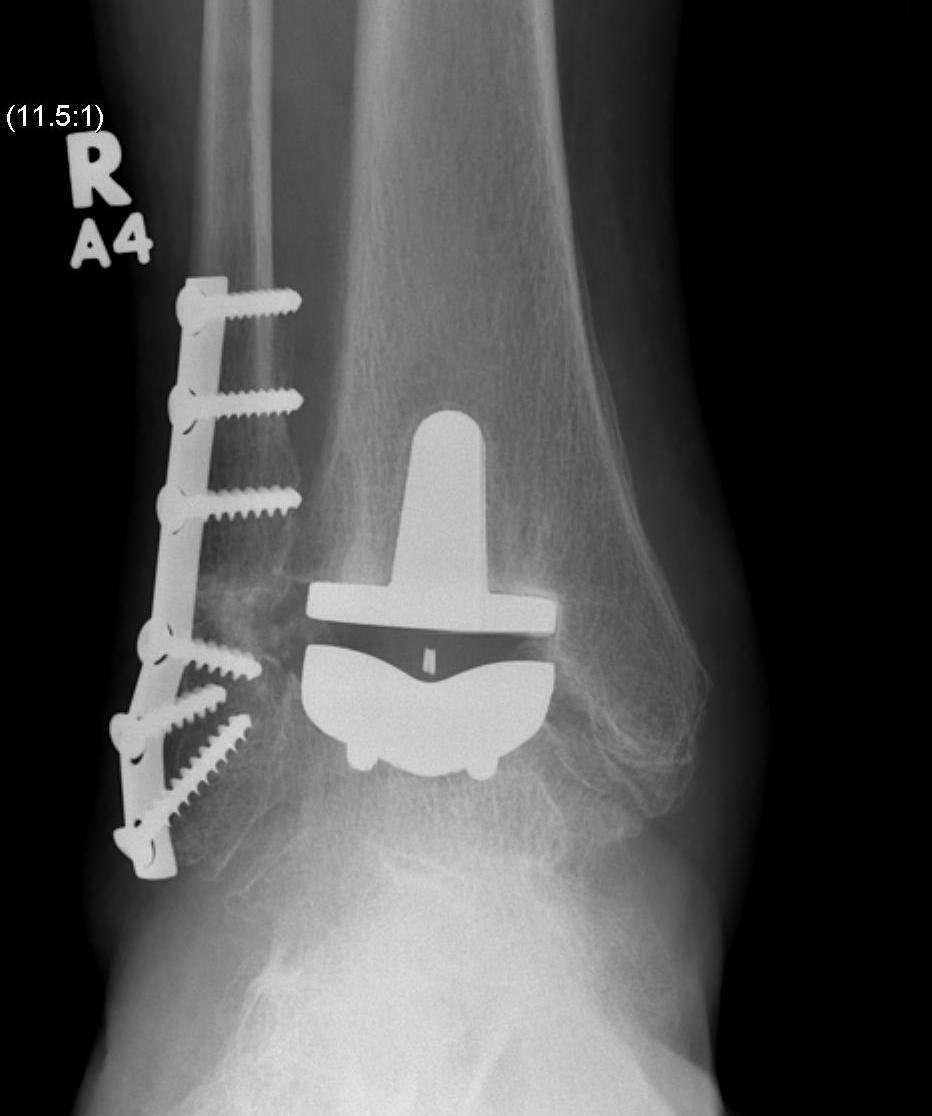

Ankle ArthrodesisResults

90% fusion rates

Lose

Disadvantages of Arthrodesis

Non union rates up to 12% Decreased gait speed Poor mobility over uneven surfaces Ankle Arthroplasty